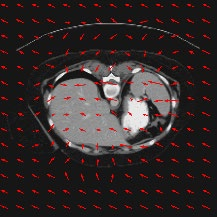

Transformers have made remarkable progress towards modeling long-range dependencies within the medical image analysis domain. However, current transformer-based models suffer from several disadvantages: (1) existing methods fail to capture the important features of the images due to the naive tokenization scheme; (2) the models suffer from information loss because they only consider single-scale feature representations; and (3) the segmentation label maps generated by the models are not accurate enough without considering rich semantic contexts and anatomical textures. In this work, we present CASTformer, a novel type of generative adversarial transformers, for 2D medical image segmentation. First, we take advantage of the pyramid structure to construct multi-scale representations and handle multi-scale variations. We then design a novel class-aware transformer module to better learn the discriminative regions of objects with semantic structures. Lastly, we utilize an adversarial training strategy that boosts segmentation accuracy and correspondingly allows a transformer-based discriminator to capture high-level semantically correlated contents and low-level anatomical features. Our experiments demonstrate that CASTformer dramatically outperforms previous state-of-the-art transformer-based approaches on three benchmarks, obtaining 2.54%-5.88% absolute improvements in Dice over previous models. Further qualitative experiments provide a more detailed picture of the model's inner workings, shed light on the challenges in improved transparency, and demonstrate that transfer learning can greatly improve performance and reduce the size of medical image datasets in training, making CASTformer a strong starting point for downstream medical image analysis tasks.